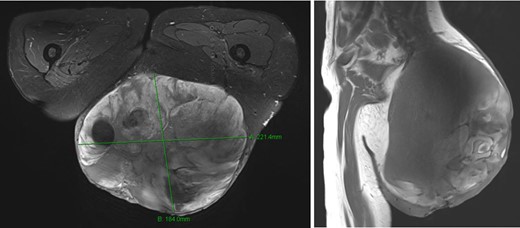

A woman 36 years of age presented with a painless, slowly growing mass of the left buttock (Fig. 1). Magnetic resonance showed an inhomogeneous tumor of 10 × 8.5 × 6 cm3 in size suspicious for myxoid sarcoma (Fig. 2). Biopsy was recommended. However, the patient refused and was lost for follow-up. Three an a half years later, the anemic patient was referred again, now with a giant 22 × 19 × 24 cm3 measuring, foul, ulcerating and bleeding tumor (Fig. 3), partly infiltrating the gluteus maximus muscle (Fig 4). Myxoid sarcoma was confirmed by three deep punch biopsies in local anesthesia followed by swift surgical resection.

Clinical situation in March 2018 (3 and a half years after primary finding). A gigantic tumor arose of the left gluteal region, partially necrotic, foul and with bleeding ulceration.

Magnetic resonance imaging showed a very large tumor of the left gluteal region, further infiltrating the left gluteus muscle and now with infiltration of the skin.

The patient was put in prone position under general anesthesia and the operating site desinfected with Povidone Iodine solution. The operation field was additionally covered with an Iodine impregnated incision drape to further minimize bacterial contamination. The skin was incised circumferentially, minimally 1 cm away from the palpable tumor mass, until reaching the fascia of the gluteus maximus muscle. The tumor was then resected circumferentially including parts of the gluteus maximus muscle and its fascia leaving the sciatic nerve and the external anal sphincter untouched. Wound closure was achieved after epifascial mobilization, followed by uneventful wound healing and an acceptable aesthetic result (Fig. 5). Pathohistological workup confirmed wide resection (R0) of an intermediate grade myxoid liposarcoma Grad 2 according to the French Federation of Comprehensive Cancer Centers (FFCCC), weighing 5.6 kg and measuring 26 × 24 × 15 cm3. After interdisciplinary discussion at the in-house sarcoma board, no radiation therapy was recommended.